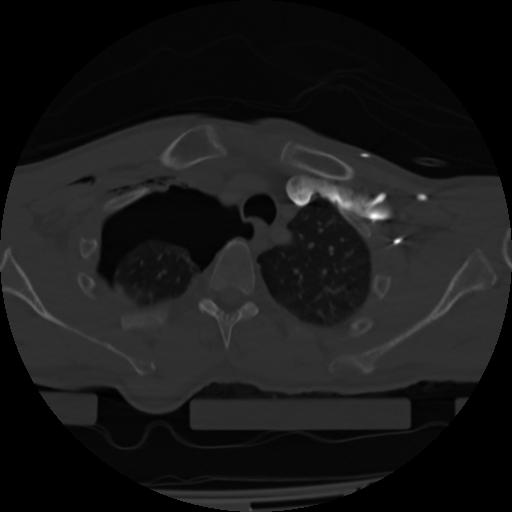

21 ANGIO,CE,Axial,3.0,ANGIO,,